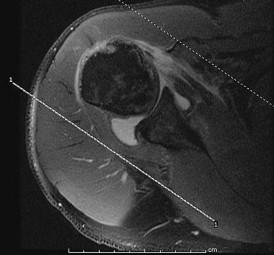

A 27-year-old professional volleyball attacker complains of subtle posterior shoulder pain and a subjective decrease in hitting power. Physical exam reveals normal active elevation, 5/5 strength in shoulder abduction, but notable weakness (3/5) in external rotation with the arm at the side. MRI of the shoulder is ordered. Based on the physical exam findings, where is the isolated neural compression most likely located, and what is the classic associated pathologic finding?

Explanation

The patient exhibits isolated weakness in external rotation (infraspinatus) with preserved abduction (supraspinatus). This indicates suprascapular nerve entrapment distal to the branches supplying the supraspinatus, specifically at the spinoglenoid notch. In overhead athletes, this is classically associated with a paralabral cyst extending from a posterior superior labral tear (SLAP lesion).